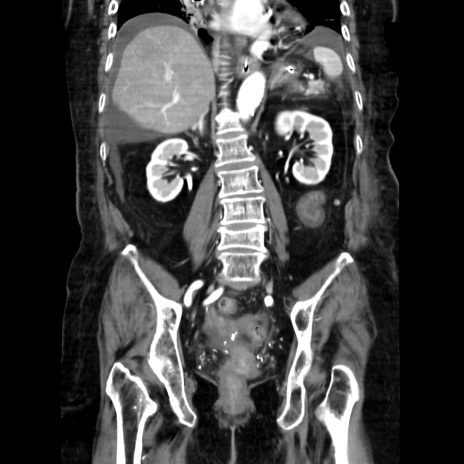

症例40(冠状断像)

【症例】90歳代女性

【主訴】腹痛・嘔吐

【現病歴】 食欲低下、嘔吐があり昨日他院受診。肺炎と診断され入院となる。入院後より腹部全体に圧痛あり。胃管留置され経過みていたが、症状持続するため、

当院転院となる。

【既往歴】胸椎圧迫骨折、胆石症

【身体所見】腹部:中央に激痛あり、圧痛あり、反跳痛不明

【データ】WBC 17100、CRP 18.82

冠状断像